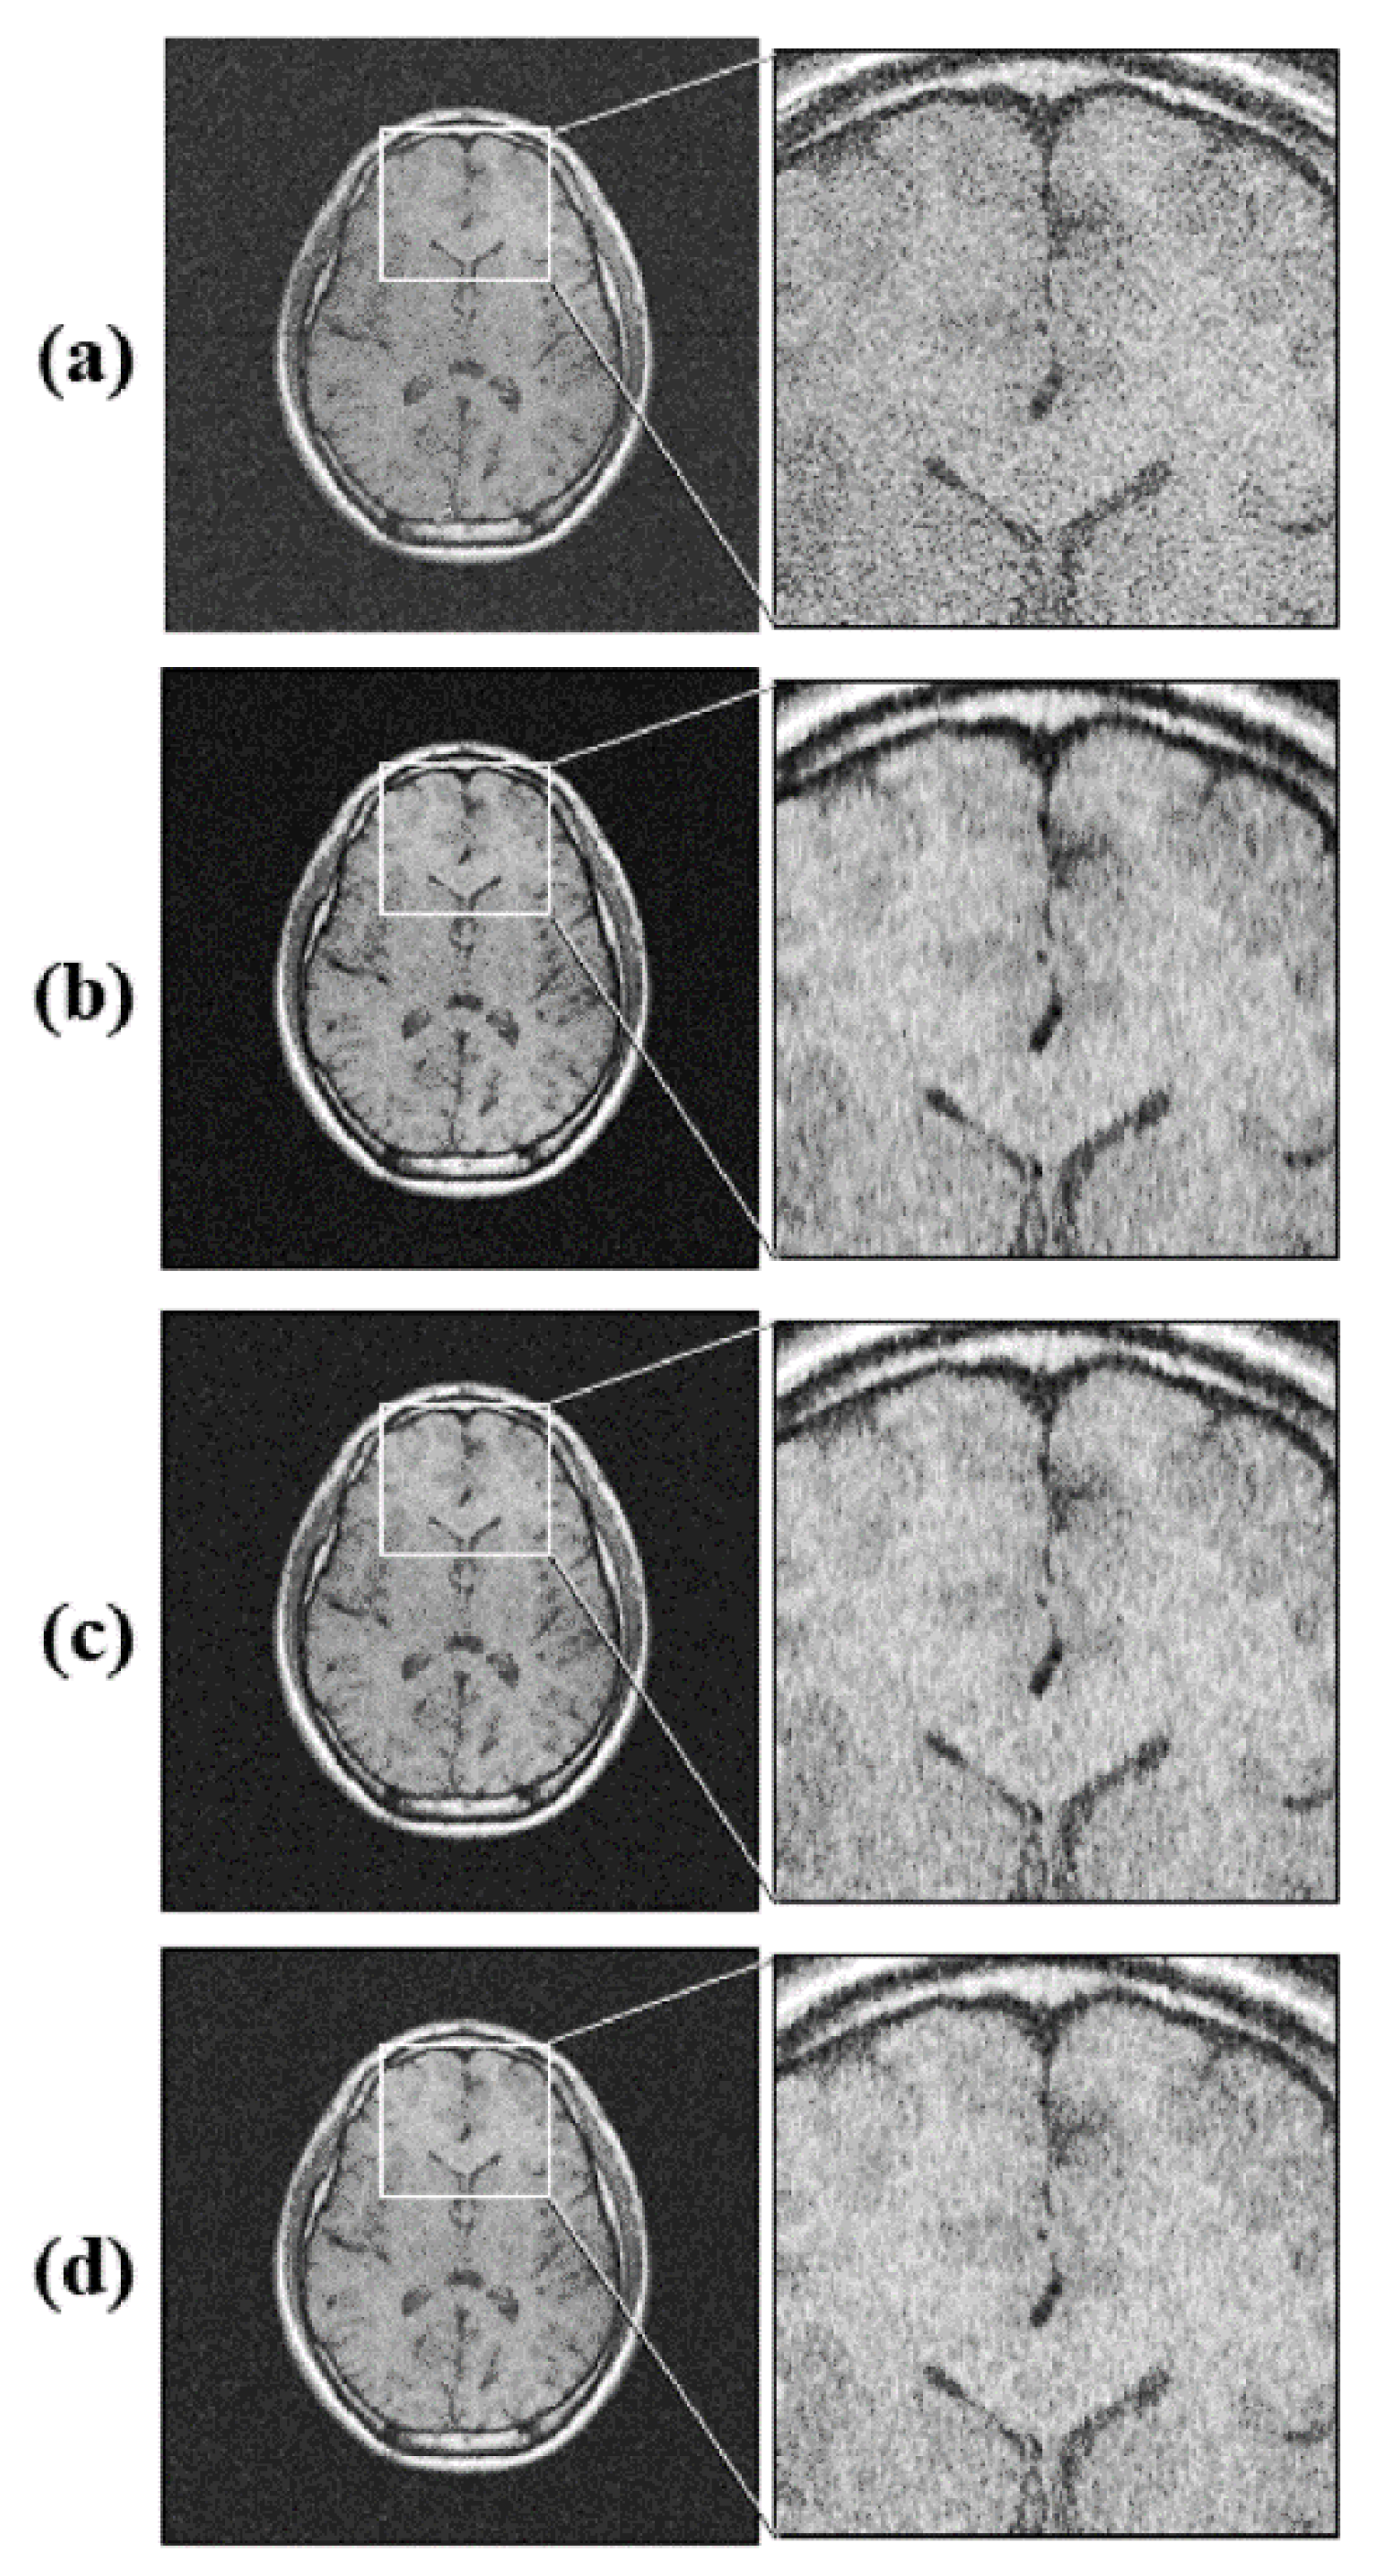

Figure 2.

Simulation for k-space undersampling effects. (a) A full sampling image; (b) image reconstructed from the 25% undersampling mask applied to the full sampling dataset; (c) image reconstructed from the 35% undersampling mask applied to the full sampling image; (d) image reconstructed from the 45% undersampling mask applied to the full sampling image.

The results of the simulation performed using the full k-space sampling dataset obtained from the human participant showed that the CSA images became noisy as the undersampling ratio increased, and the SNR also decreased as the number of sampling lines increased. The SNRs in the white and gray matter regions were 10.41, 9.80, 8.86, and 5.57, and 9.69, 9.35, 8.46, and 5.59, at 25%, 35%, 45%, and 100% (i.e., full k-space sampling), respectively (Table 3). Note that the SNRs in the white and gray matter were 5.57 and 5.59, respectively, for the full k-space. In addition, it was visually confirmed that a circular ringing artifact occurred at the top of the CSAM image, which was most severe at the 25% undersampling ratio (Figure 2). Ringing and blurring artifacts were also found in the CSAM and CSAKS images, although there were some differences depending on the undersampling ratio. However, they were not found in the CSAKC image (Figure 3).

There were no artifacts in the full k-space sampling for in vivo human imaging, but undersampling simulation images generated from the full k-space dataset demonstrated ringing and blurring (Figure 2). Furthermore, this study also used the brain phantom to investigate whether aliasing in CSA images was an artifact caused by motion or by a lack of sampling lines. The results showed that the smaller the number of sampled lines (i.e., 25%), the greater the number of artifacts. As a result of the analysis, we found that no artifacts occurred in images with full k-space sampling, but that aliasing occurred according to the undersampling ratio even in a motionless brain phantom. This can be interpreted as the result of insufficient k-space sampling numbers, not motion. Furthermore, although CSAKC required a shorter acquisition time, it had no image blurring and a high signal intensity compared with a full k-space image (Figure 5).